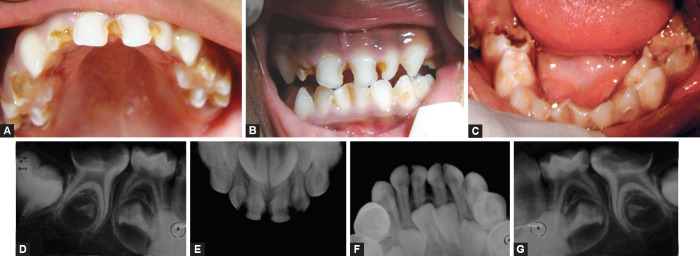

Aim and background: Myelomeningocele (MMC), the most severe form of spina bifida, is a congenital malformation of the spinal cord and brain, often associated with type II Arnold-Chiari malformation. This condition leads to significant complications such as hydrocephalus, cerebrospinal fluid (CSF) leakage, mobility impairment, and bladder/bowel incontinence. These issues, along with social and financial burdens, profoundly affect patients and their families. Children with MMC are also at higher risk of dental neglect, increasing the likelihood of severe oral health issues like dental caries and gingival disease.

Case description: This case focuses on the dental management of a young child with MMC and type II Arnold-Chiari malformation. Due to the elevated risk of complications from general anesthesia or sedation, behavior management techniques were employed to provide comprehensive dental care. The treatment approach considered the child's medical complexities, mobility limitations, and neurosensory challenges, ensuring that oral health needs were met safely and effectively.